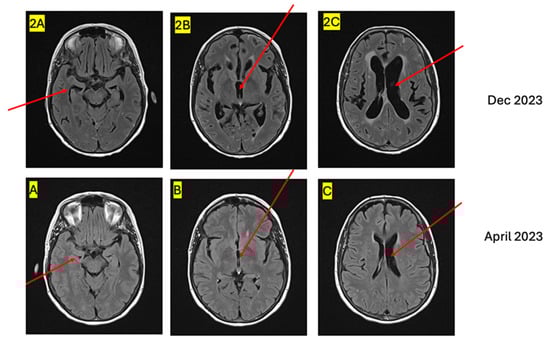

| 2023 (July) | 2023 (December) | 2024 (March) |

| New liver metastasis and significant increase in retroperitoneal disease | Leptomeningeal metastasis causing hydrocephalus | Disease progression and worsening Neurologic symptoms |

| Weekly paclitaxel | T-DXd | No further therapy |